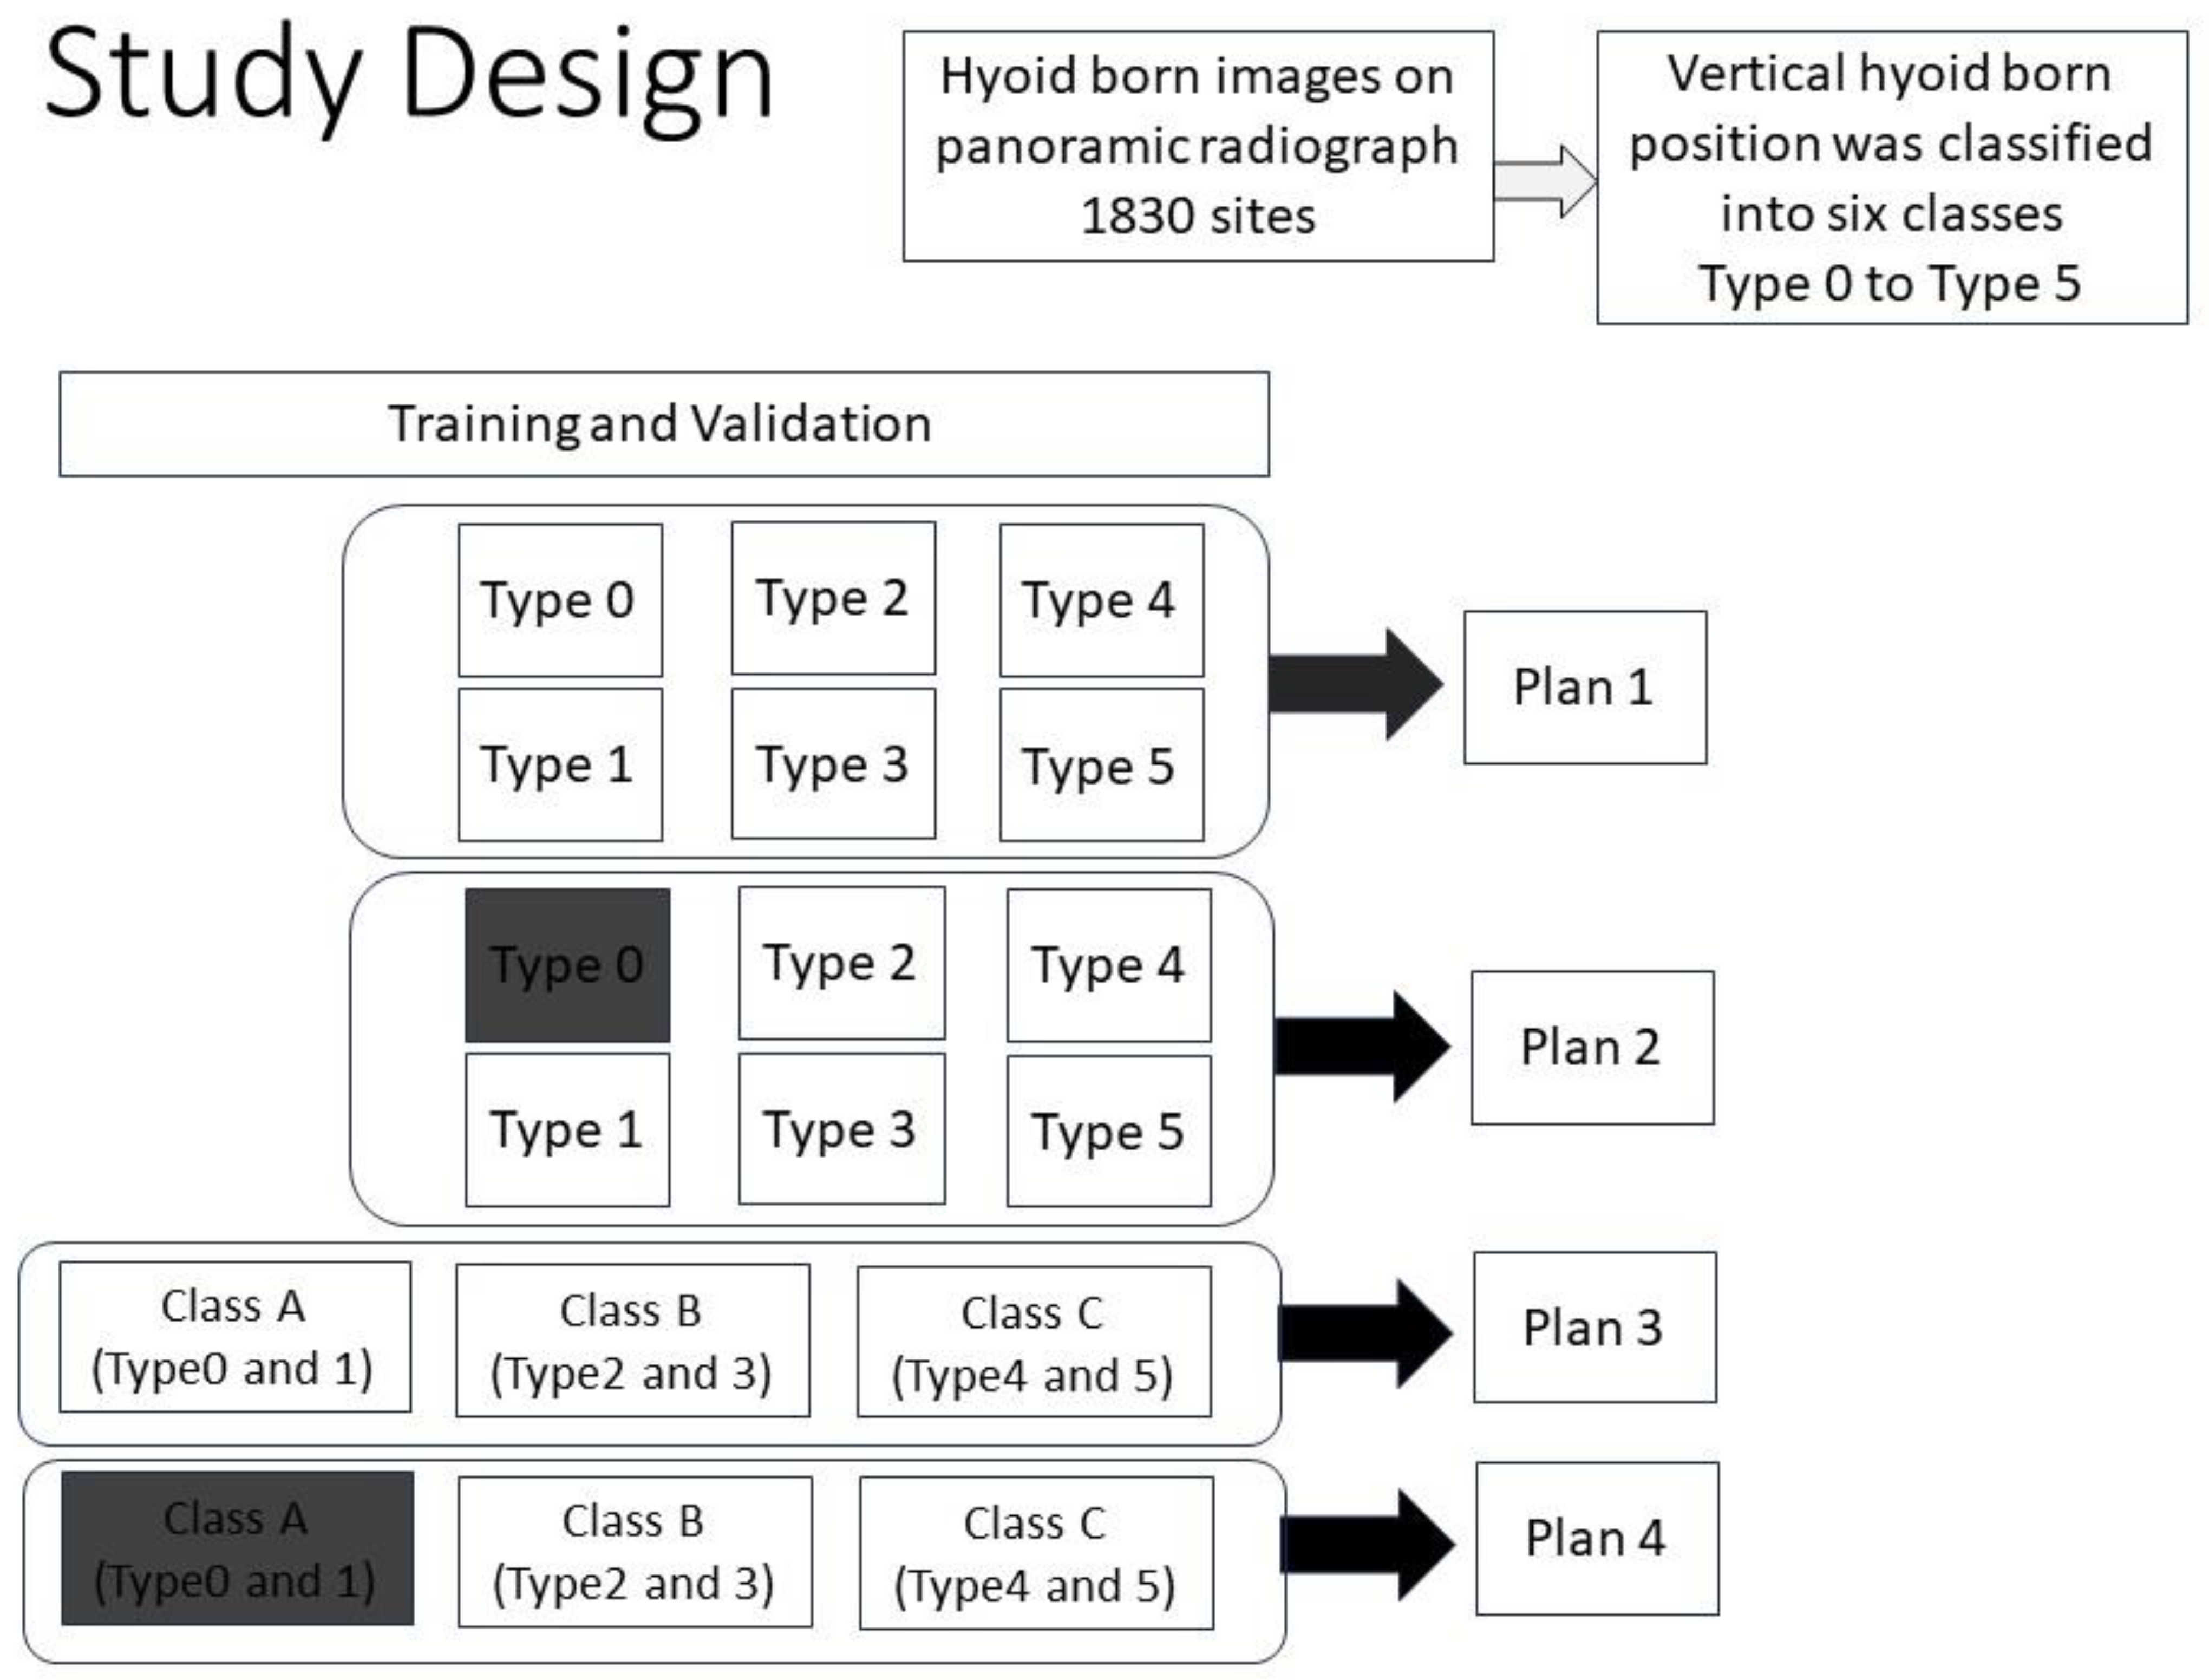

- Plan 1 (study of 6 types).

- Plan 2 (study of 5 types).

- Plan 3 (study of 3 Classes)

- Plan 4 (study of 2 Classes)